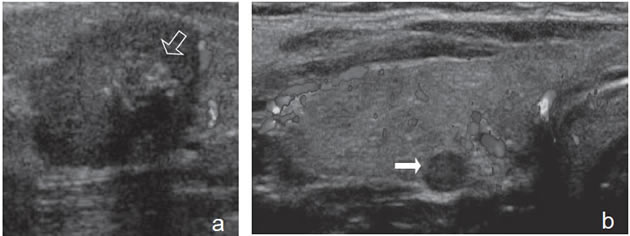

Un nódulo que tiene un componente quístico significativo, usualmente es un nódulo benigno hiperplástico, que ha acumulado abundante coloide (Figura 2a) o bien, un nódulo sólido que ha experimentado un proceso de degeneración colicuativa o hemorragia (Figura 2b). El coloide o el contenido líquido de un nódulo se ve anecogénico (negro en la imagen ecográfica) y las estructuras sólidas se ven ecogénicas (distintos tonos de grises), siendo la ecogenicidad similar al del parénquima tiroideo. En un nódulo sólido la ecoestructura y la ecogenicidad pueden ser variables. En general, la frecuencia de carcinoma es muy baja en nódulos quísticos13 y la mayoría de los carcinomas se presentan como nódulos sólidos (Figura 2c).

Figura 2. a) Quiste coloideo anecogénico y focos ecogénicos (flecha) con artefacto en cola de cometa; b) Nódulo mixto sólido-quístico (cabezas de flechas). Imagen vegetante (flecha) adherida a un tabique que se proyecta al lumen; c) Comparación entre el aspecto ecográfico de un cáncer papilar sólido (flecha abierta) y un quiste coloideo anecogénico.